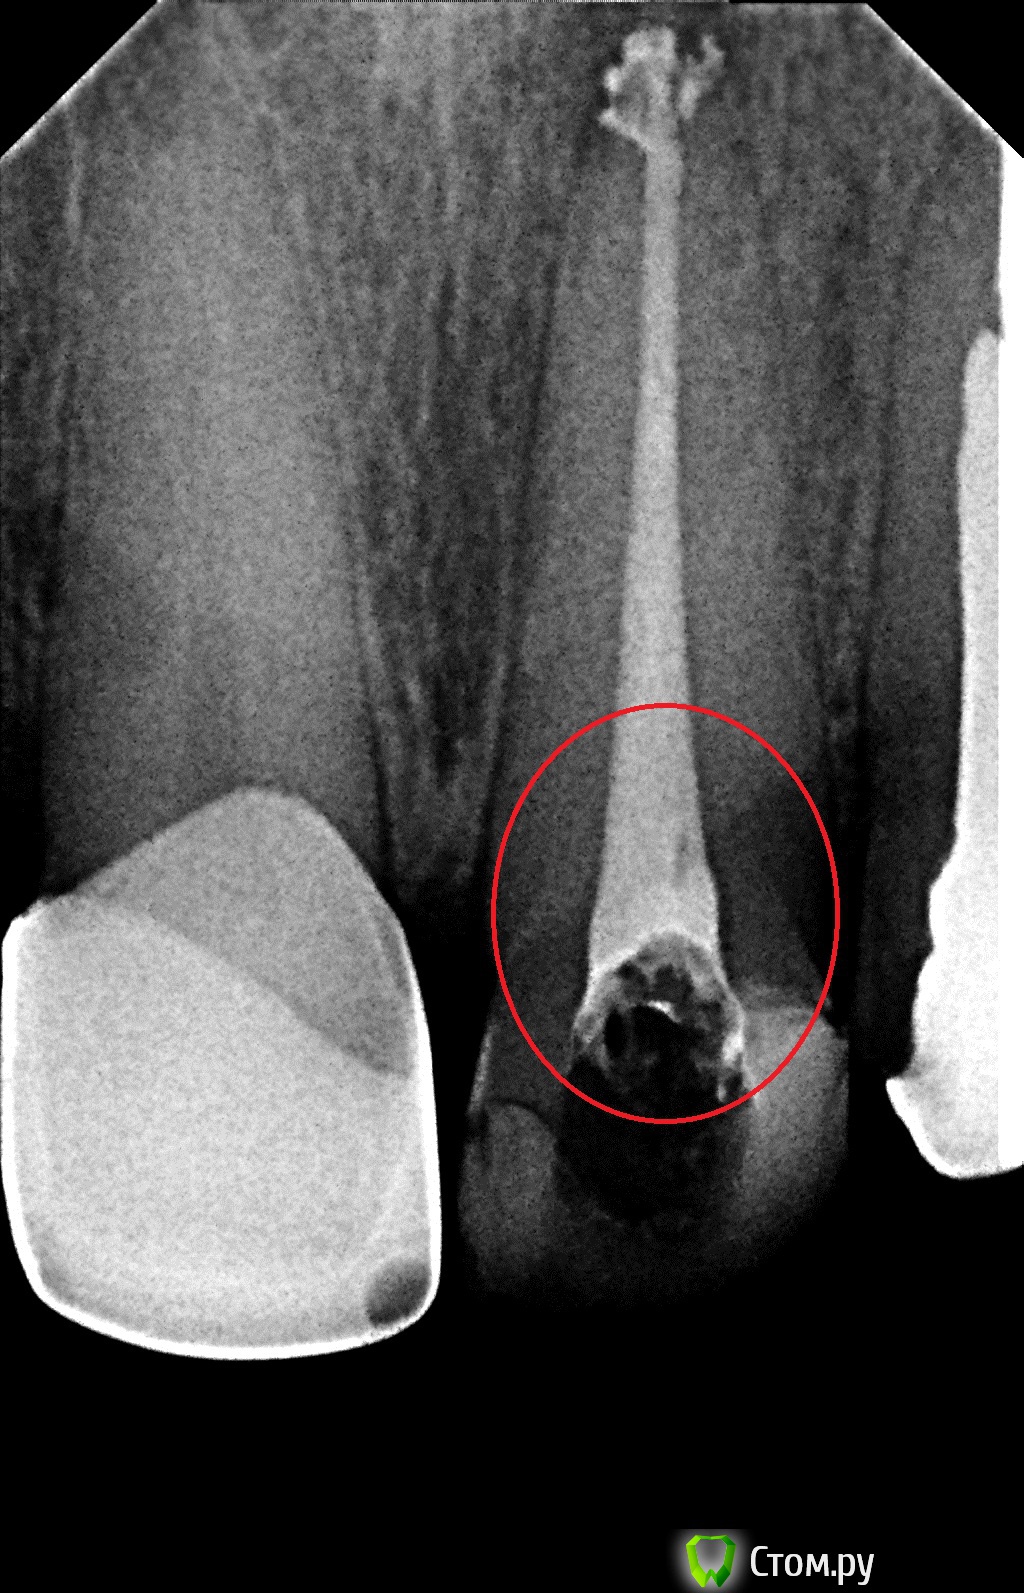

Татьяна Николаевна Опубликовано 20 мая, 2014 Поделиться Опубликовано 20 мая, 2014 Здравствуйте. Недавно пролечила верхний резец в частном кабинете. Сейчас пришла протезироваться в поликлинику, врач- ортопед сказала, что зуб пролечен плохо, материал вышел из канала, надо перелечить. Меня он никак не беспокоит.В кабинете где я его лечила пломбировали его по моему каким то горячим способом. Снимок прилагаю, зуб отметила. Ссылка на комментарий

sydnik Опубликовано 20 мая, 2014 Поделиться Опубликовано 20 мая, 2014 Здравствуйте. материал немного вышел,но ничего страшного в этом нет.может сходите на консультацию к другому ортопеду 1 Ссылка на комментарий

Гарриевич Опубликовано 20 мая, 2014 Поделиться Опубликовано 20 мая, 2014 Пролечен зуб в пределах нормы. Если ортопед сказал именно "перелечить", то смените ортопеда и перелечивать не надо будет) 1 Ссылка на комментарий

red_butler Опубликовано 20 мая, 2014 Поделиться Опубликовано 20 мая, 2014 Плюсуюсь, хорошо пролечен Ссылка на комментарий